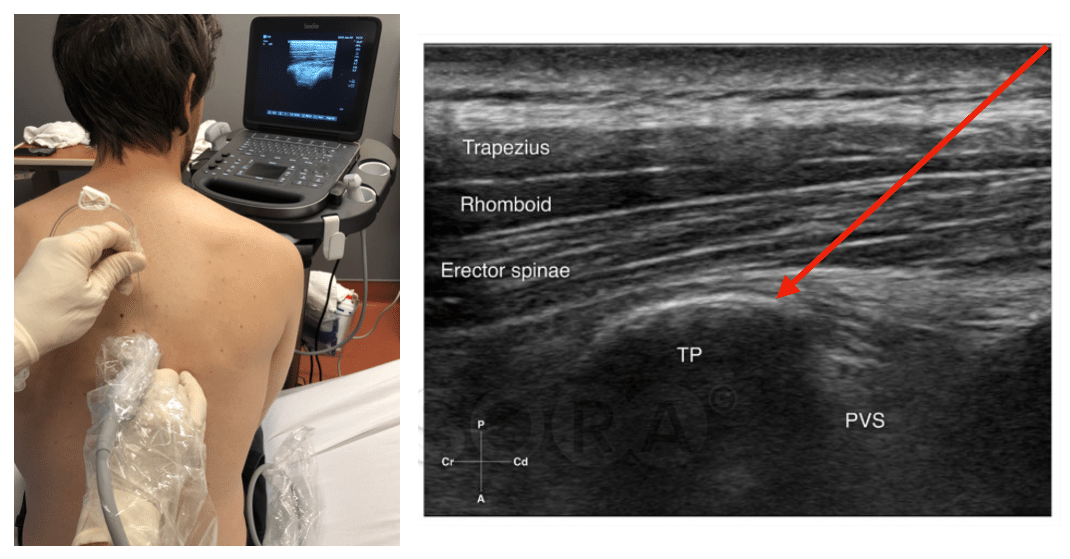

a Positioning and scanning during erector spinae plane (ESP) block What Is A Erector Spinae Block Espb achieves a block of the posterior, lateral, and anterior thoracic wall. Erector spinae plane (esp) block overview : The erector spinae plane block (espb) is one of seven ‘plan a’ blocks proposed by regional anaesthesia uk, covering the key areas of commonly encountered surgeries and acute. The esp block, like the transversus abdominis plane (tap) or the pectoralis (pecs). What Is A Erector Spinae Block.

Ultrasound image of erector spinae plane block. TP transverse process What Is A Erector Spinae Block The esp block, like the transversus abdominis plane (tap) or the pectoralis (pecs) and serratus plane blocks, is. The erector spinae plane (esp) block is a newer regional anesthetic technique that can be used to provide analgesia for a variety of surgical procedures or to manage acute or chronic pain. The erector spinae plane block (espb) is a technically simple. What Is A Erector Spinae Block.